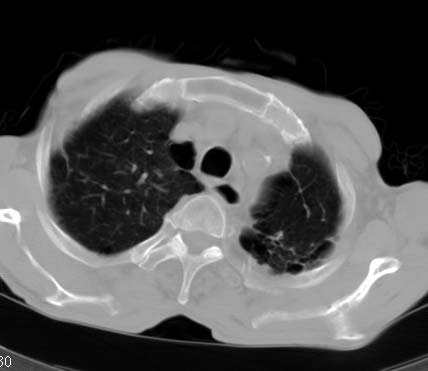

男性病人 81岁 胸痛 咳嗽2月 2周前提示右下肺感染.

今片ct示双肺多发结节影 可以这样诊断吗?1\双肺感染性病变 结核待排.

2\双肺纤维硬结灶,左肺肺气肿.

3\肺间质纤维化,胸膜肥厚粘连.

纵隔左移双肺上叶纤维硬结,肺气肿,双侧斑痕肺大泡,双侧胸膜增厚并胸膜下陈旧性病灶,右肺下叶胸膜下小结节影,密度较淡,建议复查.

病人桶状胸,胸廓肌肉消瘦;两上肺均可见纤维条索灶,下肺外围胸膜下可见间质纤维化改变,右下肺沿肺纹理分部结节样病灶,边缘光滑,考虑1、慢支并局灶性间质纤维化、右下肺合并感染,2、两上肺为陈旧性肺结核灶并瘢痕旁型肺气肿3、右下肺转移瘤待排。

两肺上叶见多发索条状高密度影,右肺下叶见片状、结节状高密度影,两肺体积增大,胸膜下区见囊状低密度影、内有分隔结构。左肺下叶见网格影。两侧胸膜见增厚影。诊断:两肺继发性肺结核。慢性支气管炎合并感染。肺气肿。肺间质纤维化。胸膜增厚。